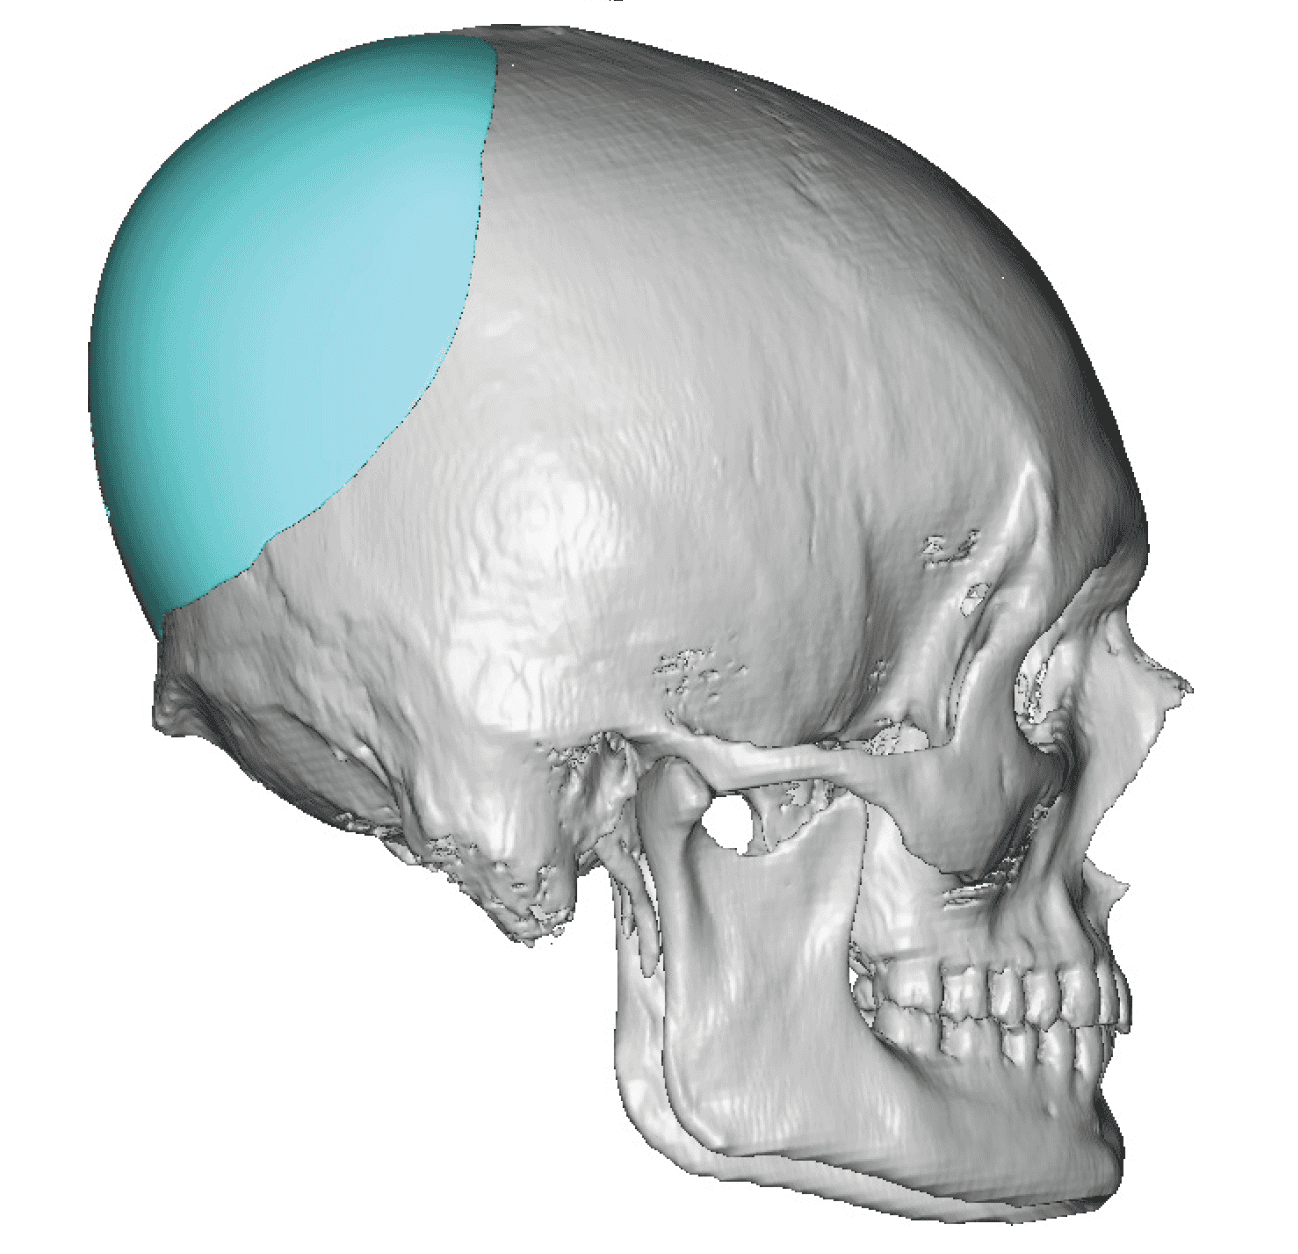

Patient 100

Desire for reshaping of an asymmetric flat back of the head in a shaved head male.

A combined back of the head reshaping procedure was done with a custom skull implant, sagittal ridge reduction and a right temporal muscle reduction.

Desire for reshaping of an asymmetric flat back of the head in a shaved head male.

A combined back of the head reshaping procedure was done with a custom skull implant, sagittal ridge reduction and a right temporal muscle reduction.